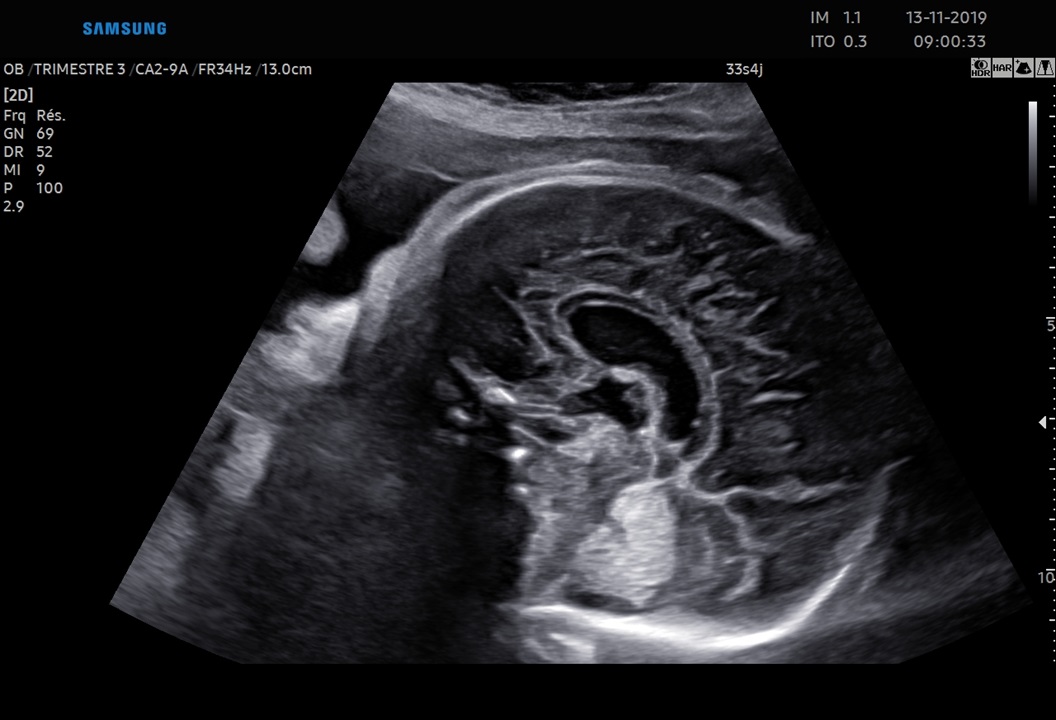

Les sondes de technologie S-Vue™ disposent d'une sensibilité accrue et d'une bande passante plus large que les sondes conventionnelles. Elles garantissent une résolution d’image optimale, même chez les patientes techniquement difficiles. De plus la petite taille et la légèreté de ces sondes améliorent les conditions d'examen au quotidien.

Obstétrique, gynécologie, abdomen, pédiatrie